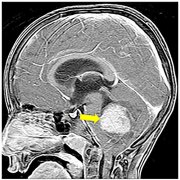

脑积水,顾名思义就是指脑中的水,只不过这个水并不是真的水...

颅内蛛网膜下腔或脑室内的脑脊液异常积聚,使其一部分或全部...